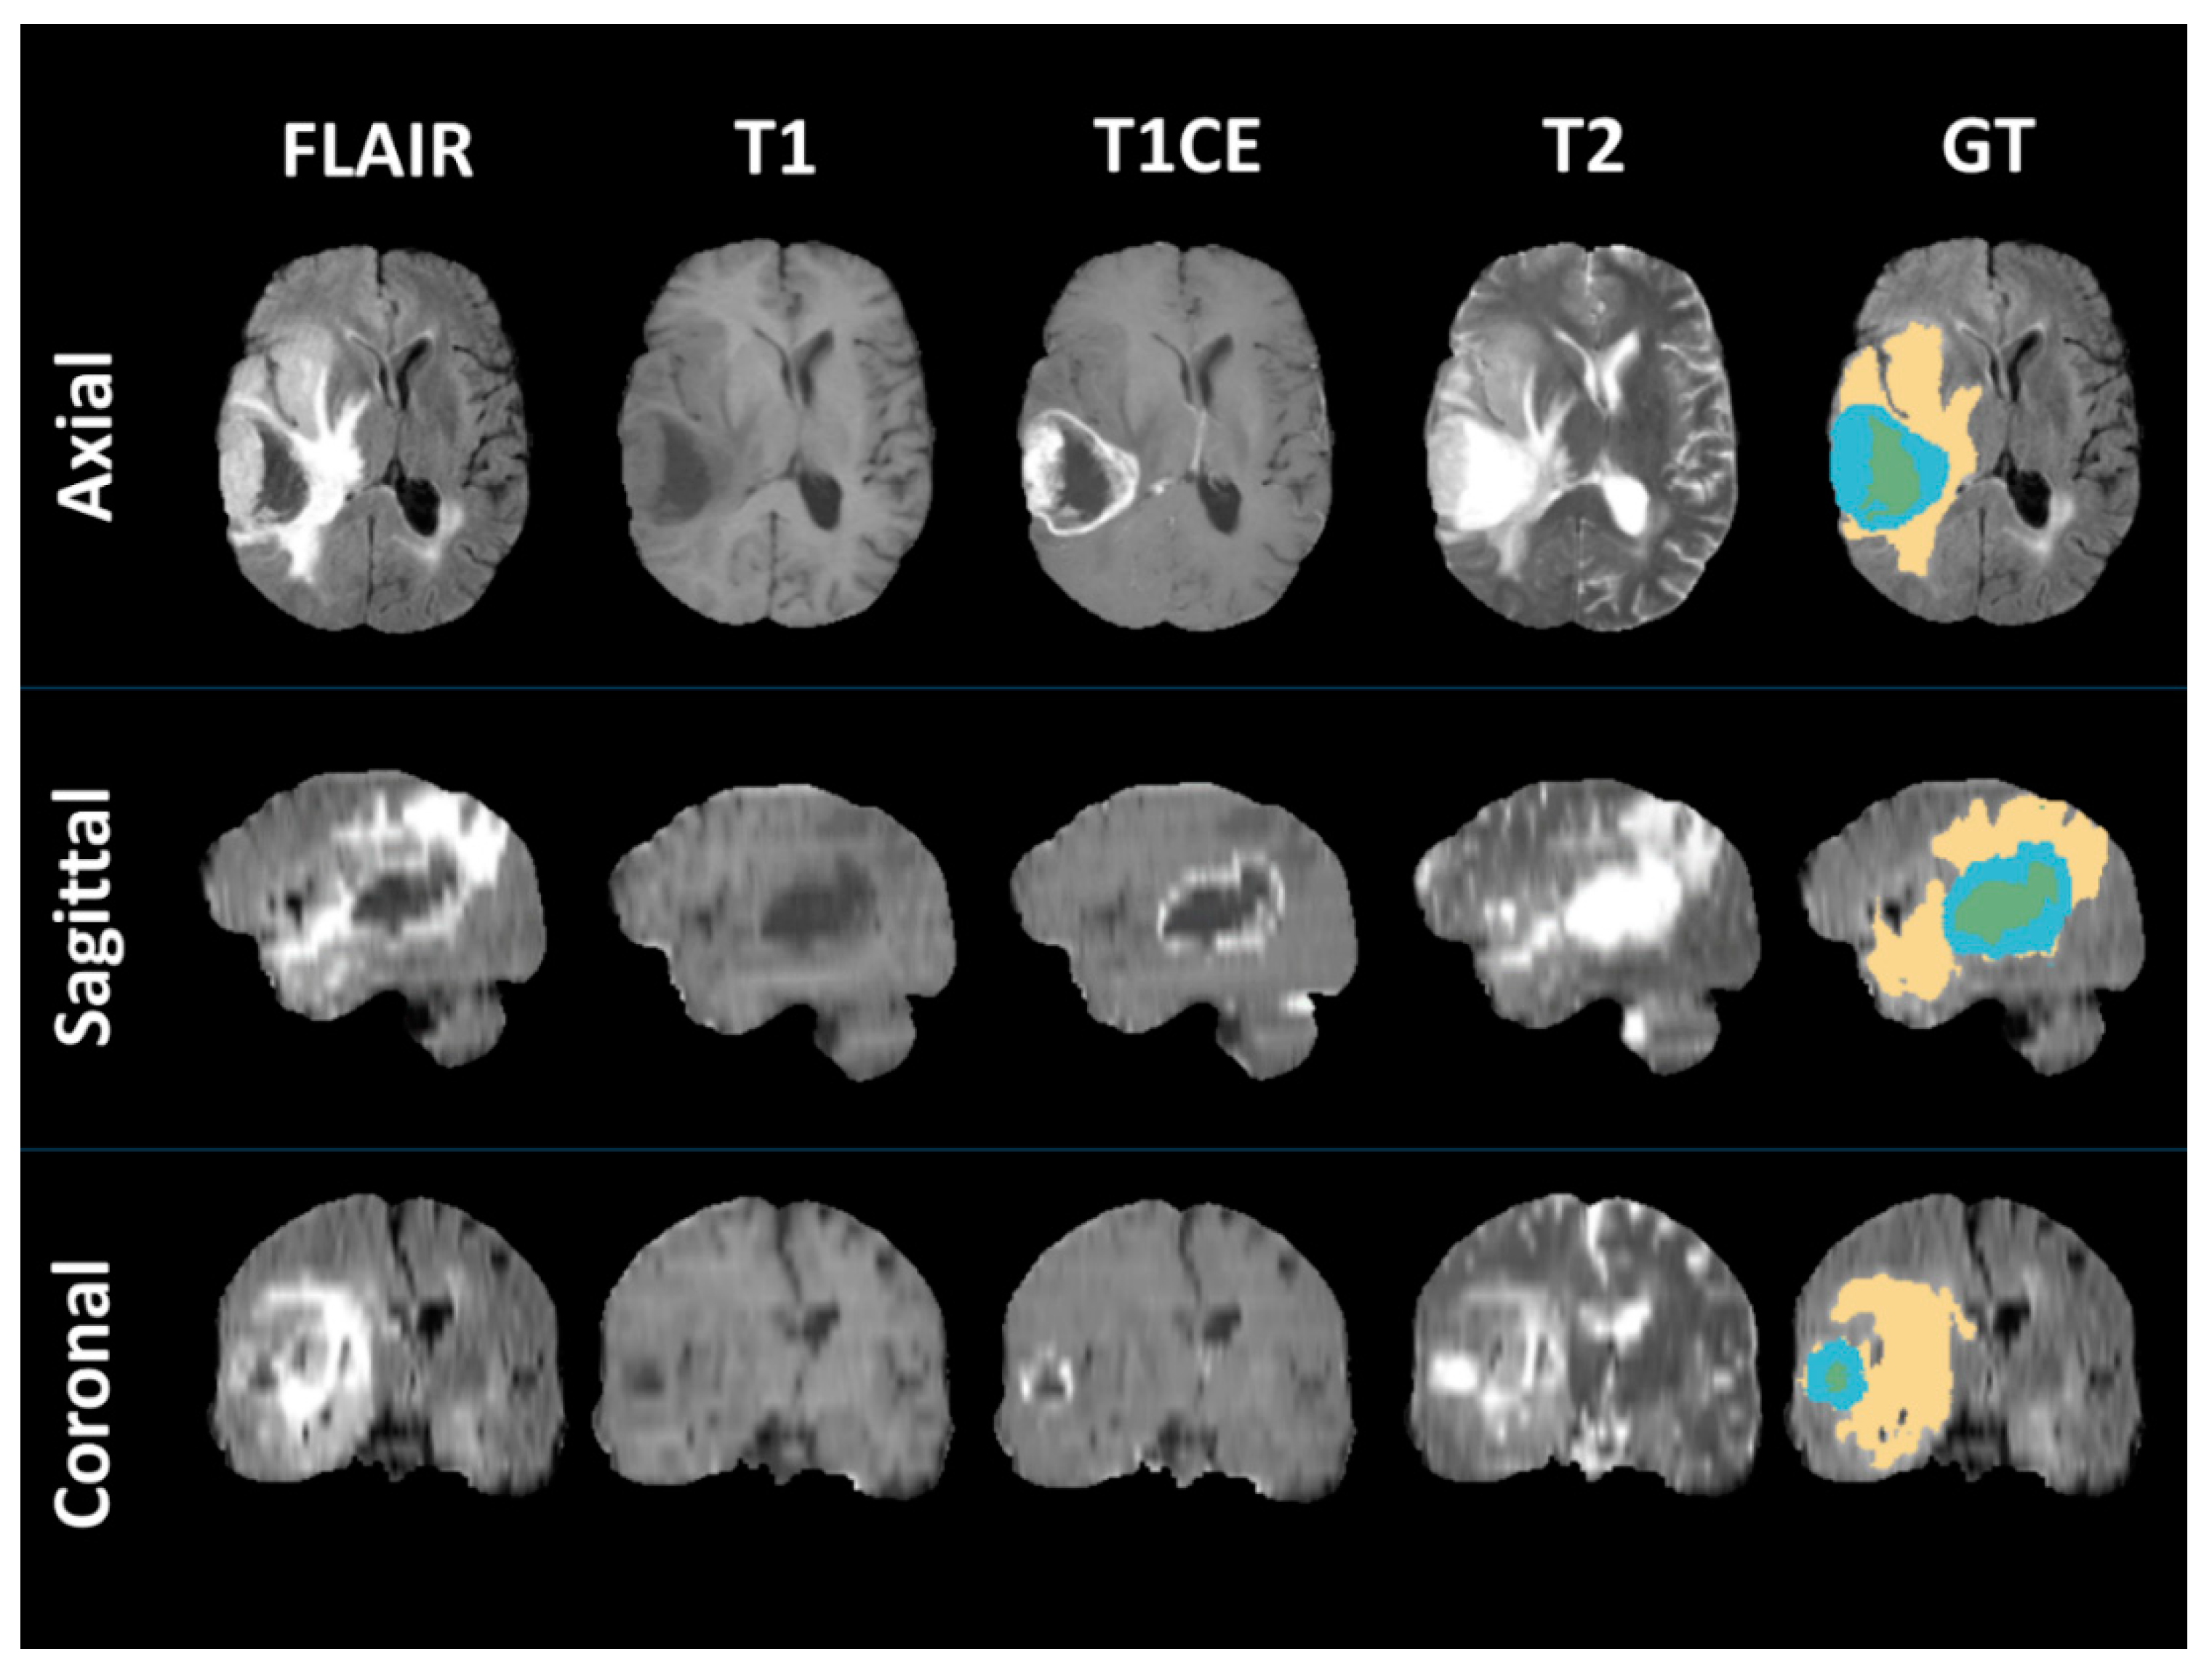

4.2. MRI Segmentation and Radiomics Features